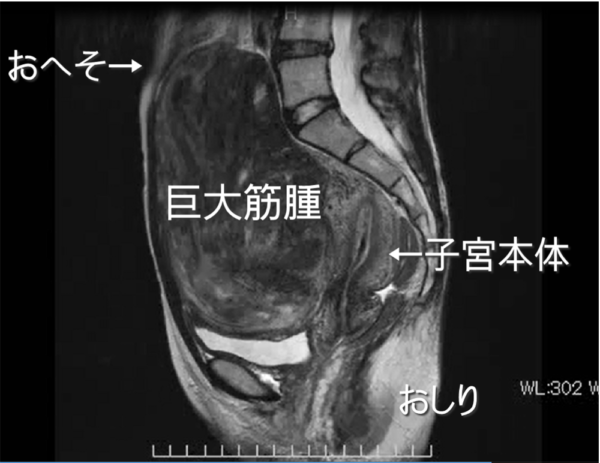

下のMRIは、下腹部を体の中心で縦割りにしたイメージです。巨大筋腫が偽閉経療法で小さくなり腹腔鏡で摘出できたケースです。17cmの巨大筋腫はおへそを超え、後に子宮が見えます。小さくなったとはいうものの摘出した筋腫は1022gありました。